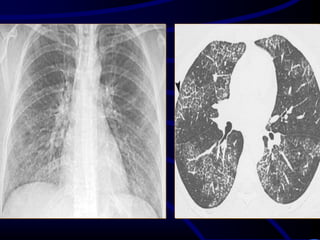

A 54-year-old female nonsmoker complained of

shortness of breath on exertion and a dry

cough.

What is the MOST

LIKELY diagnosis?

A. RB_ILD.

B. Non specific interstitial

fibrosis

C. IPF.

D. CVD

E. Subacute hypersensitivity

pneumonitis.

hypersensitivitySubacuteE.

.pneumonitis